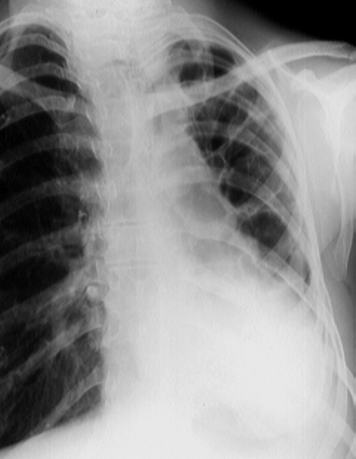

Rx toracică, incidență P-A

DESCRIERE:

la nivelul hemitoracelui stg → hipertransparență fără desen vascular pulmonar, cu colabarea plămânului spre hil, care este conturat de o linie fină (pleura viscerală)

caracter expansiv → deplasarea mediastinului de partea opusă

diafragm deplasat în jos

lărgirea spațiilor intercostale

DX: pneumotorax

DD:

emfizem pulmonar - desen vascular păstrat

bulă gigantică de emfizem - nu se văd pleura viscerală și plămânul colabat